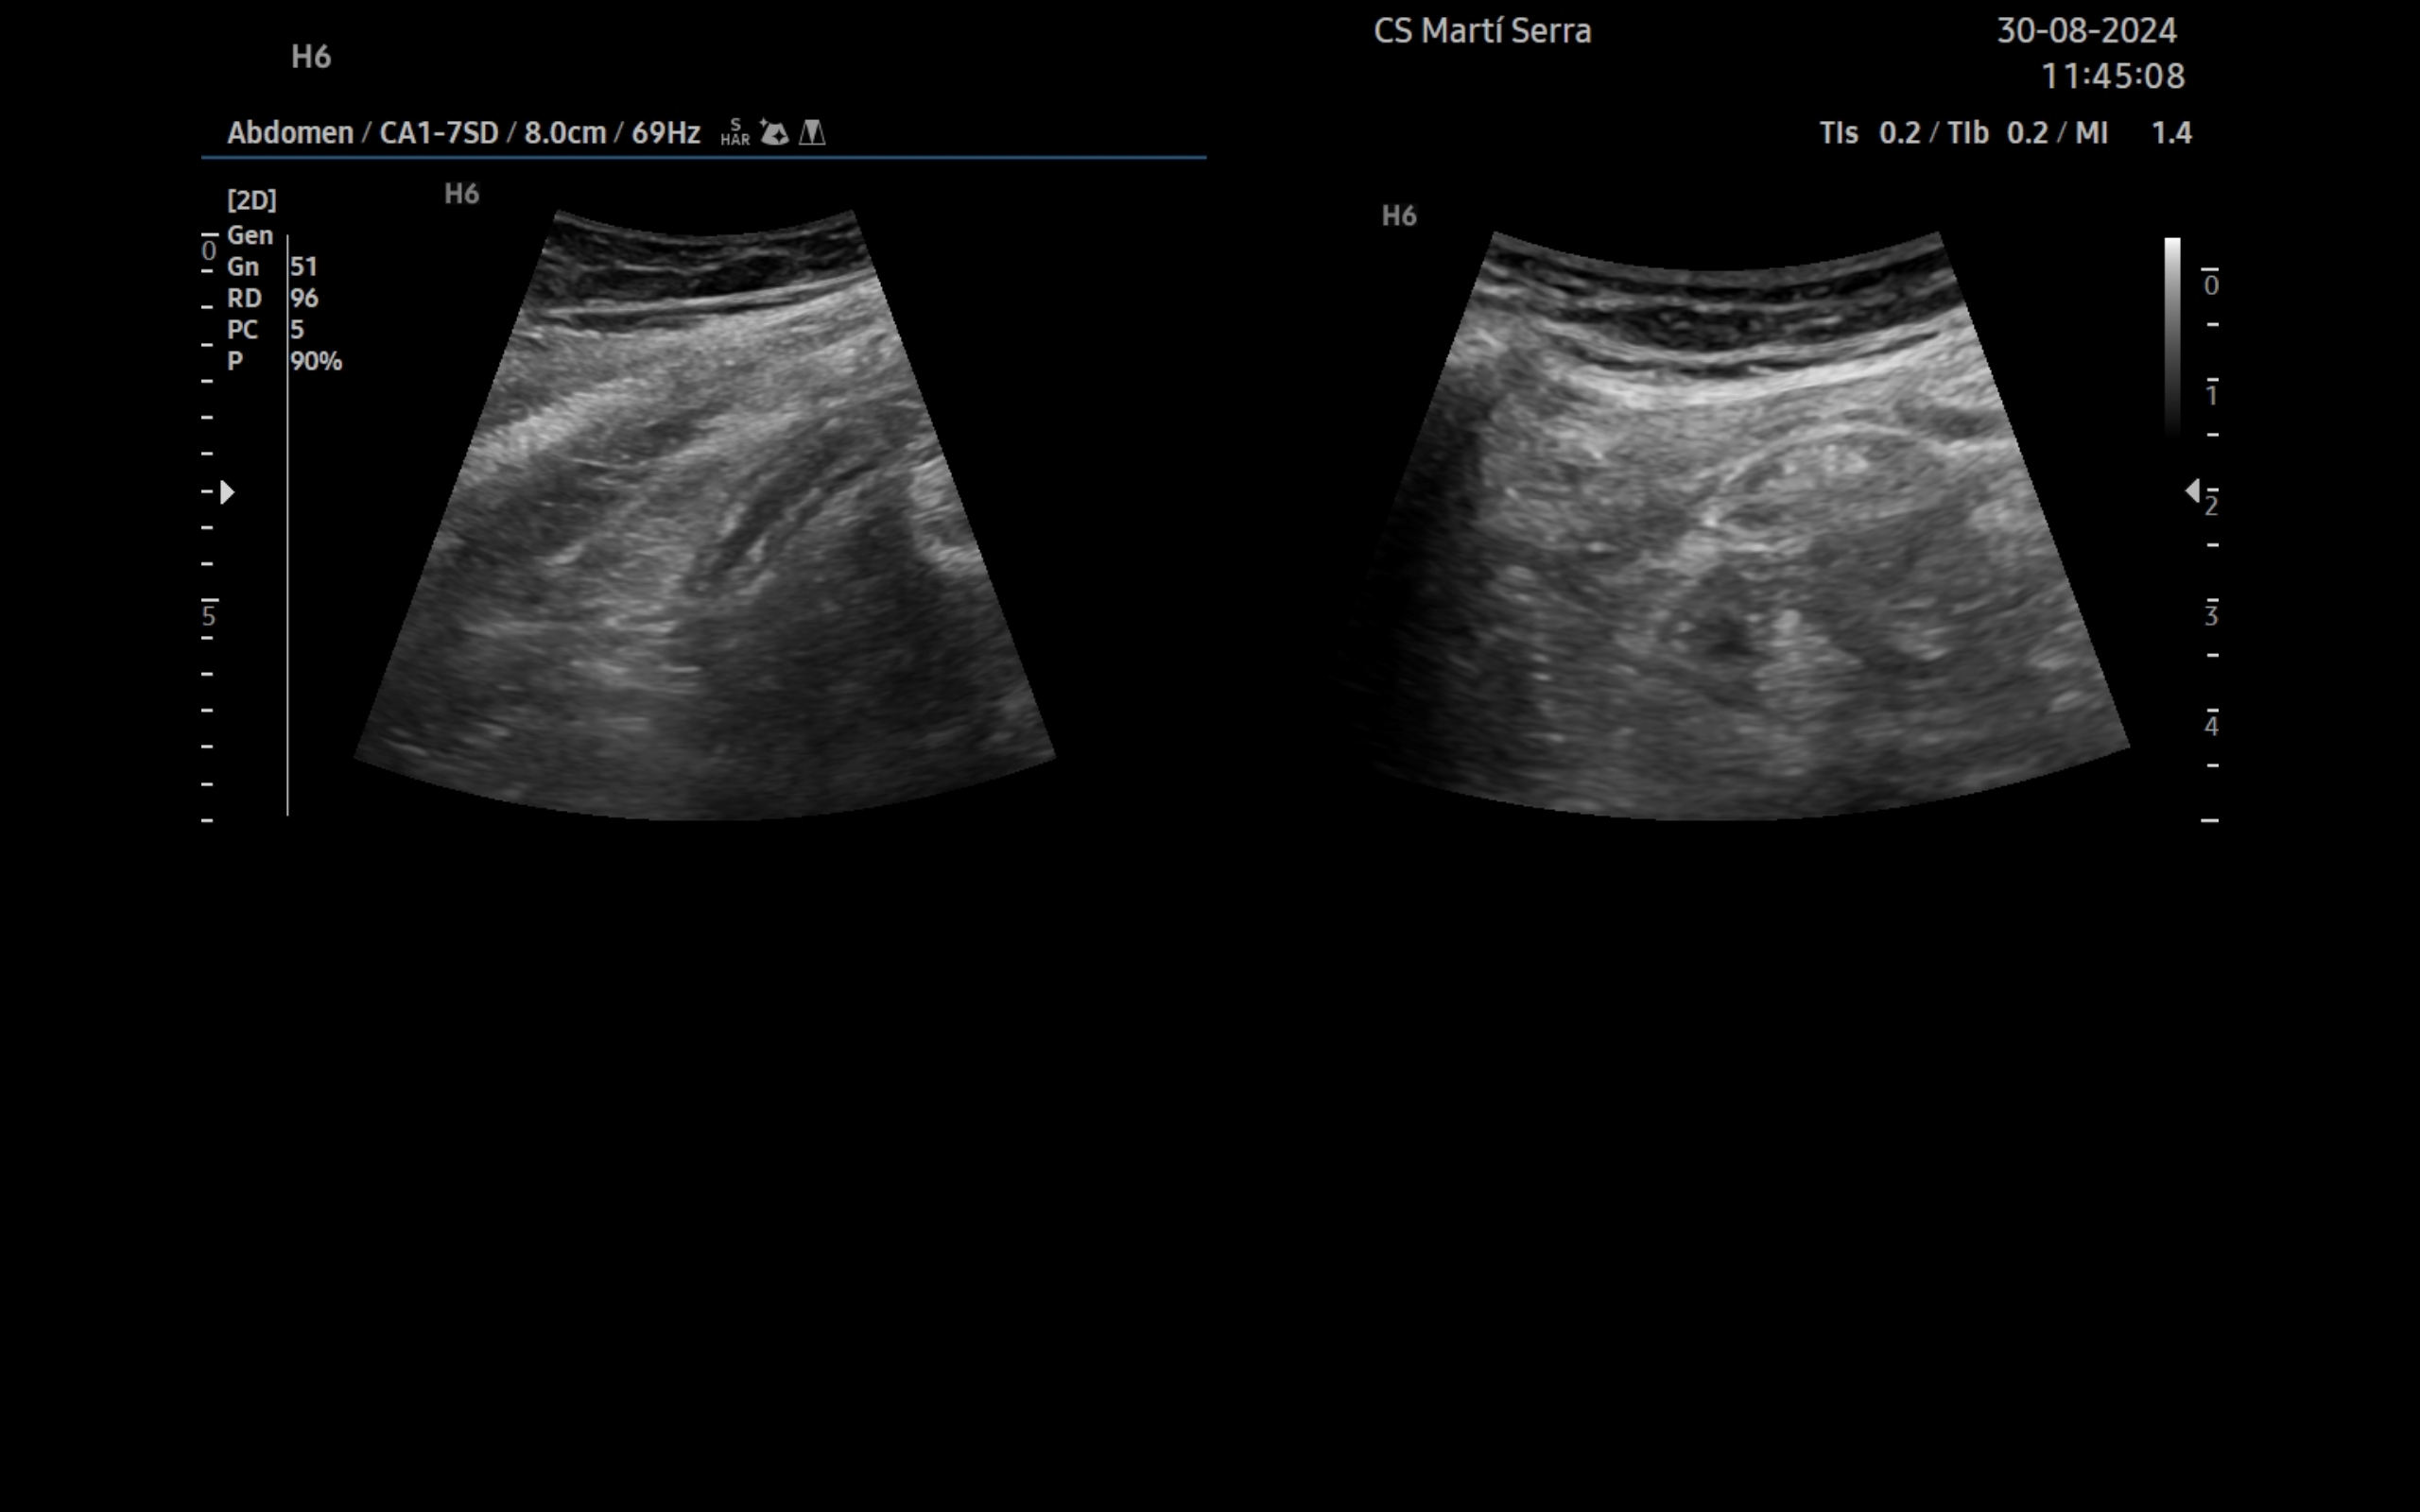

Ecografía clínica:

Imagen hiperecogénica con sombra en interior de vesícula biliar, hígado, páncreas, bazo y riñones sin alteraciones, vejiga orina poco replecionada. Llama la atención mínima imagen anecogénica en fondo de saco de Douglas. Apéndice visible en fid con diámetro 1,07 cm con captación aumentada con apendicolito con fenómeno centelleo.